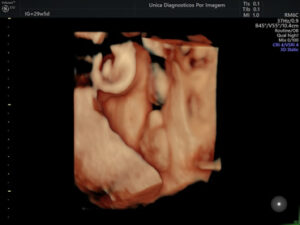

Exame importante que tem como objetivo avaliar a anatomia do feto e detectar possíveis malformações. Deve ser realizado preferencialmente realizado